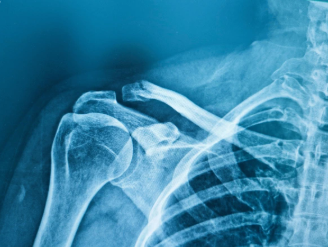

Fractures of the Shoulder & Clavicle

Shoulder and clavicle fractures involve breaks in the bones comprising the shoulder complex including the clavicle (collarbone), proximal humerus (upper arm bone), and scapula (shoulder blade). These fractures result from traumatic injuries and vary widely in severity from simple non-displaced fractures treated conservatively to complex comminuted fractures requiring surgical reconstruction. Clavicle fractures are most common, typically occurring in the middle third from falls or direct trauma. Proximal humerus fractures are the third most common fracture in older adults after hip and wrist fractures, often resulting from falls in patients with osteoporosis. Scapula fractures are rare, typically occurring only with high-energy trauma like motor vehicle accidents.

X-rays are essential for diagnosis showing fracture location (clavicle, proximal humerus, scapula), fracture pattern (simple, comminuted, displaced), number of fracture fragments, displacement and angulation degree, and associated injuries. Multiple views (AP, lateral, scapular Y for shoulder) ensure complete assessment. CT scan provides detailed evaluation for complex proximal humerus fractures showing number and position of fragments, humeral head involvement and impaction, glenoid fractures, and surgical planning for complex reconstruction. MRI rarely needed acutely but may evaluate rotator cuff tears associated with fractures, particularly in younger patients. Classification systems (Neer for proximal humerus, Allman for clavicle) guide treatment based on fracture characteristics. Repeat imaging during healing monitors fracture union and identifies complications like displacement or nonunion.